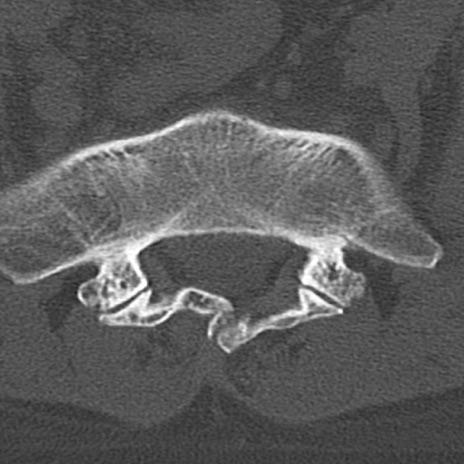

腰椎CT

矢状断像